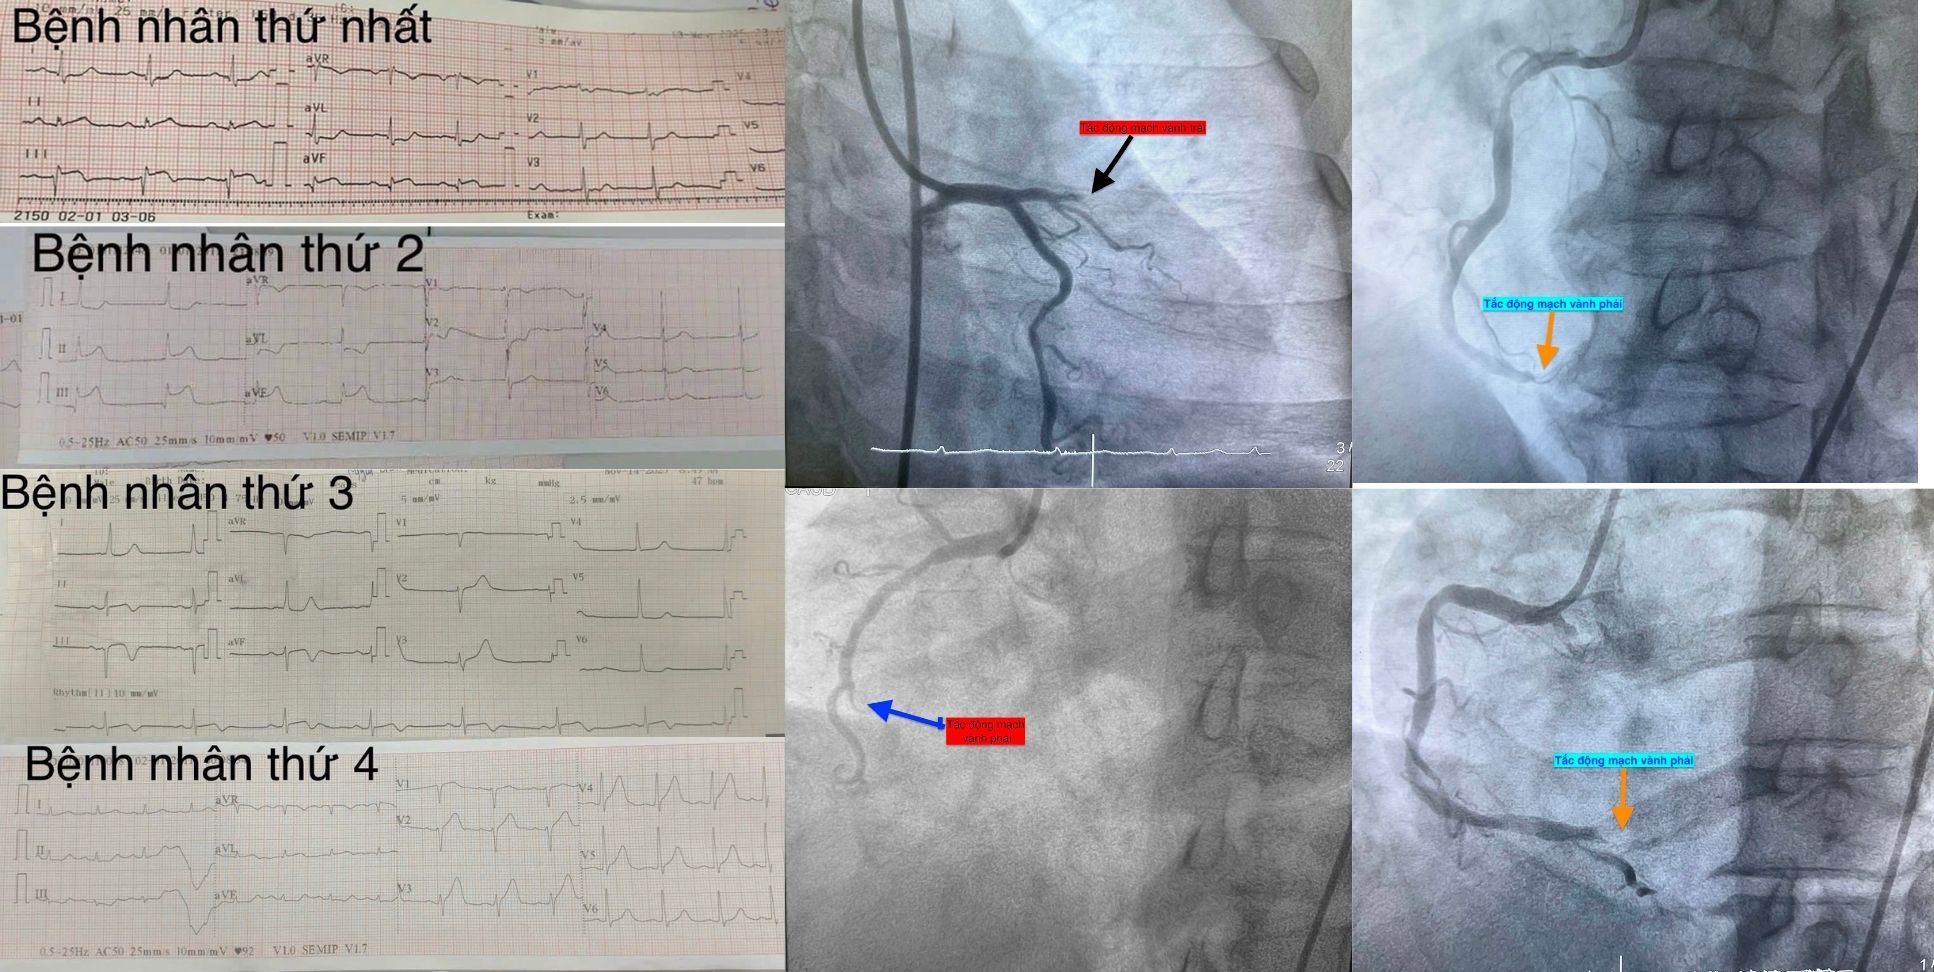

Trường hợp thứ nhất là nam bệnh nhân 51 tuổi, vào viện lúc 0 giờ 34 phút vì mệt và khó thở, không đau ngực. Chụp mạch vành phát hiện tắc hoàn toàn động mạch vành phải. Can thiệp tái thông thành công, bệnh nhân ổn định.

Trường hợp thứ hai là nam bệnh nhân 53 tuổi, nhập viện lúc 9 giờ 5 phút vì chóng mặt và nóng rát thượng vị. Điện tâm đồ ghi nhận nhồi máu cơ tim cấp vùng dưới. Chụp mạch vành xác định tắc động mạch vành phải, tái thông thuận lợi.

Trường hợp thứ ba là nam bệnh nhân 78 tuổi, vào viện lúc 15 giờ 53 phút với các triệu chứng đau ngực từng cơn trong 3 ngày, trong ngày nhập viện người bệnh đau liên tục. Điện tim gợi ý nhồi máu cơ tim cấp. Chụp mạch vành cấp cứu phát hiện tắc động mạch vành phải, đặt stent phủ thuốc thành công.

Trường hợp thứ tư là bệnh nhân nữ, 61 tuổi, mắc đái tháo đường type 2, đau ngực điển hình kèm vã mồ hôi. Điện tim chẩn đoán nhồi máu cơ tim cấp thành trước. Can thiệp tái thông động mạch thủ phạm thành công.